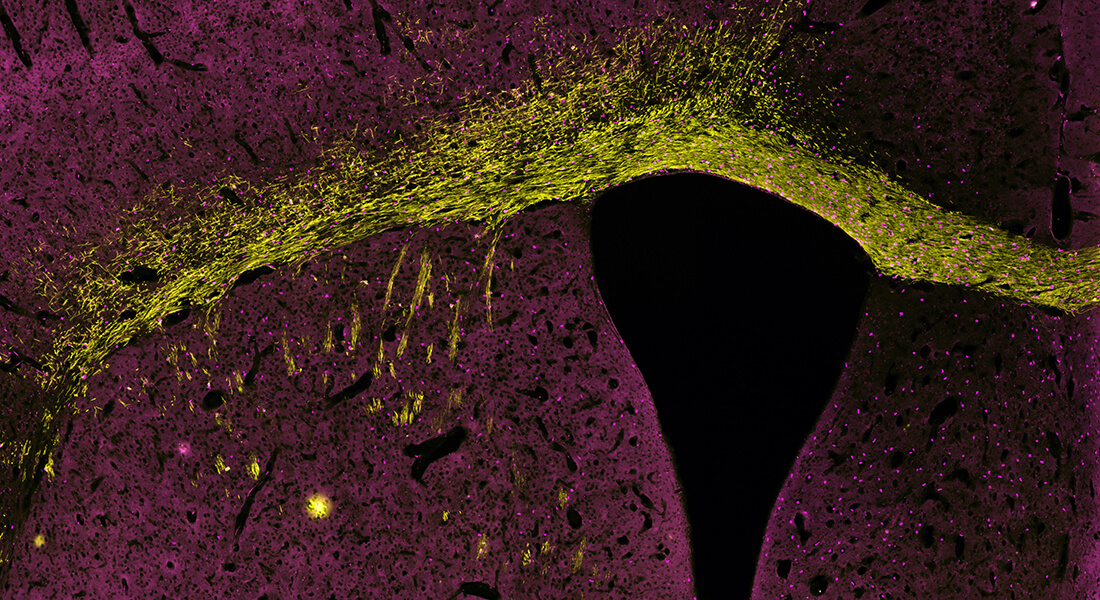

Sections of a CD140a+ cell–engrafted shiverer callosum at 12 weeks, immunostained for MBP, human GFAP and human nuclear antigen (showing robust production of hGFAP+ astrocytes as well as MBP+ oligodendrocytes).

This project focuses on defining the gene expression changes associated with in vivo remyelination by human oligodendrocyte progenitor cells, using our novel human glial chimeric brain model.

By way of background, little information is available as to the changes in gene expression or dominant pathway activation associated with the mobilization, oligodendrocyte fate commitment, or myelination by human oligodendrocyte progenitor cells during the process remyelination.

To accomplish this goal, and to do so using human cells in vivo, we have established human glial chimeras by neonatal implantation of human glial progenitor cells into the forebrains of neonatal immunodeficient mice; in these mice, the human progenitor pool outcompetes their mouse counterparts, resulting in the eventual replacement of the mouse glial progenitors by their human counterparts.

By subjecting these mice to cuprizone demyelination, and then following the resultant compensatory remyelination by the human progenitor cells, we can track remyelination by human cells in vivo, both by direct imaging, and by transcriptional analysis of sorted human progenitors. For the latter purpose, the remyelinating human progenitor are being sorted from their host brains by surface antigen-based FACS, and their transcriptional profiles assessed by both microarray and RNAseq.

These data will provide us the transcriptional events associated specifically with progenitor mobilization and remyelination, and as such should provide new targets for accelerating and potentiating this process following acute demyelinating episodes.